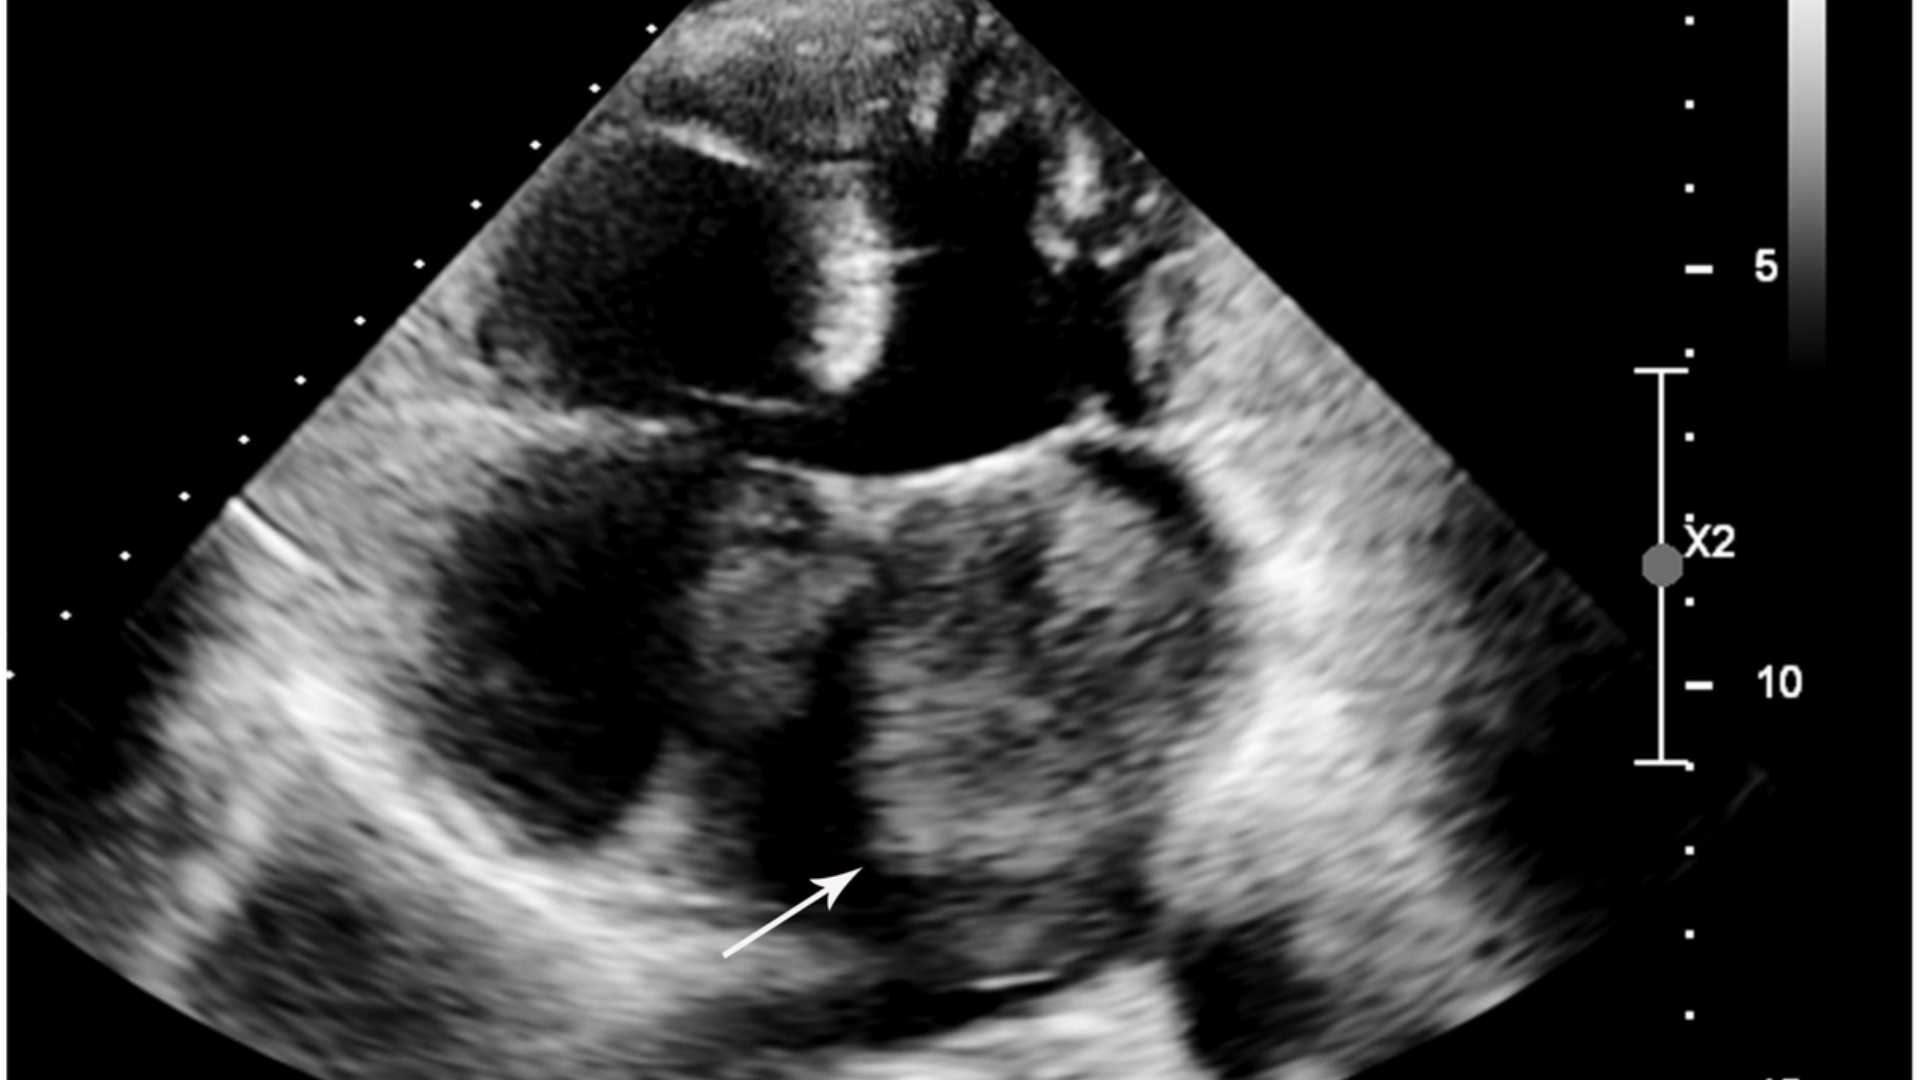

• 進階診斷:最先進的影像(例如 PET-CT、Siemens MRI)和分子剖析,以找出腫瘤的代謝漏洞。